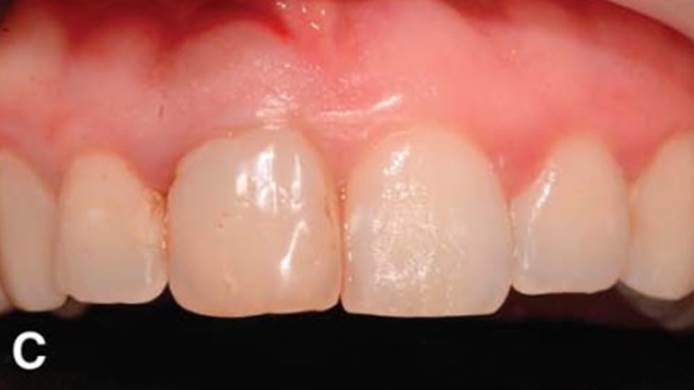

“Immediate loading of single AnyRidge implants

is a highly successful treatment modality. ”

Clinical case: Immediate post-extraction insertion of implant & immediate loading

- Courtesy of Prof. Giuseppe Luongo, Italy -

AnyRidge, immediate loading, single implant, multicenter study, maxillary anterior, Prof. Giuseppe Luongo, single replacement

AnyRidge implant system